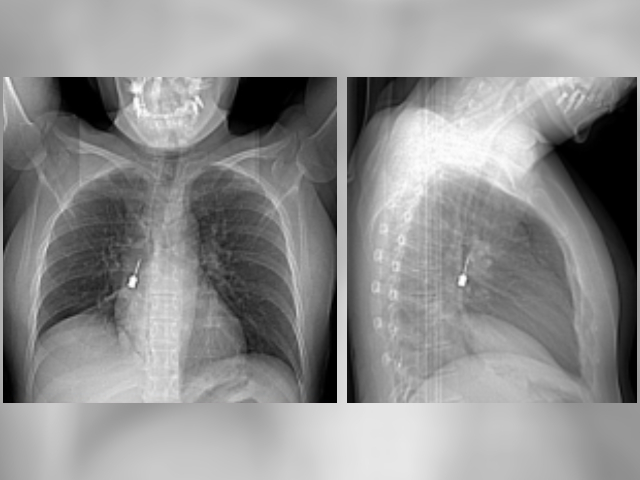

La paziente, consigliata dal medico a sottoporsi a una Tac per i sintomi persistenti, ha così scoperto la presenza di un corpo estraneo metallico bloccato nel bronco destro. Le immagini della tomografia computerizzata hanno reso evidente la situazione, spingendo i medici a ricoverarla immediatamente per una valutazione urgente. La Tac ha inoltre evidenziato un pneumomediastino, ossia la presenza di aria nello spazio tra i due polmoni, condizione che rendeva la situazione particolarmente delicata.

Il direttore dell’UOC di chirurgia toracica, Baldassare Mondello, insieme alla sua équipe e agli anestesisti, ha eseguito una complessa procedura endoscopica per rimuovere il corpo estraneo. L’oggetto, un piccolo cacciavite odontoiatrico, era stato accidentalmente inalato dalla giovane, causando i disturbi respiratori e il dolore toracico.